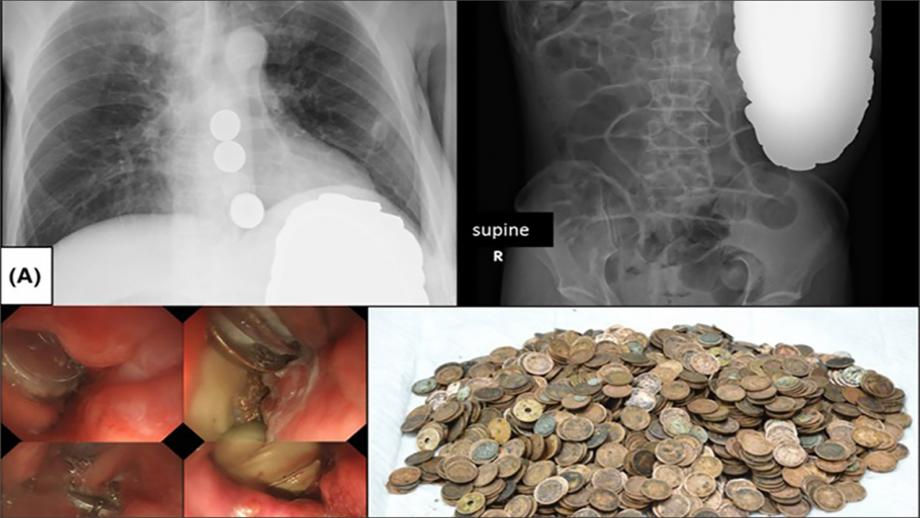

صنع ياباني الحدث في المستشفى بعدما اكتشف الأطباء أن معدته تحتوي على 1894 قطعة نقود معدنية، وزنها الإجمالي يفوق ثمانية كيلوغرامات، قبل أن يتم تشخيص إصابته بمرض يسميه الخبراء "بيكا".

وقد أثبت فحص الأشعة في مستشفى بطوكيو وجود أجسام دائرية في المعدة، وتقرر على إثر ذلك إخضاعه لعملية جراحية مستعجلة، فاكتشف الأطباء مذهولين وجود قطع نقدية معدنية داخل معدة المريض وبدؤوا على الفور استخراجها.

عثر الأطباء على 1894 قطعة معدنية بوزن يفوق ثمانية كلغ، منها 140 قطعة من فئة ين ياباني واحد، و99 من فئة الخمسة ينات، و1642 من فئة عشرة ينات، و8 من فئة خمسين ينا، وخمس قطع من فئة مئة ين، ويبلغ مجموع ما استخلص من بطن المريض نحو 157 دولارا.